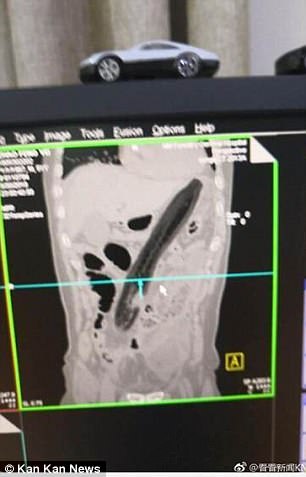

Den stora grönsaken hade flyttats upp längs den 50-åriga mannens tarmar och tillslut nått den övre buken, enligt sjukhuset.

Läkarna hävdade att när de hittade auberginen hade den nästan nått mannens hjärta.

Rapporten hävdade också att mannen hade lidit av svullnad och smärta i magen i två dagar innan han sökte vård på sjukhuset, en medicinsk rapport visade att en CT-skanning bekräftade att mannen hade en fotlångt främmande föremål i övre buken.

Röntgen visade att föremålet hade fastnat i en diagonal position och att mannens lungor var inflammerade.